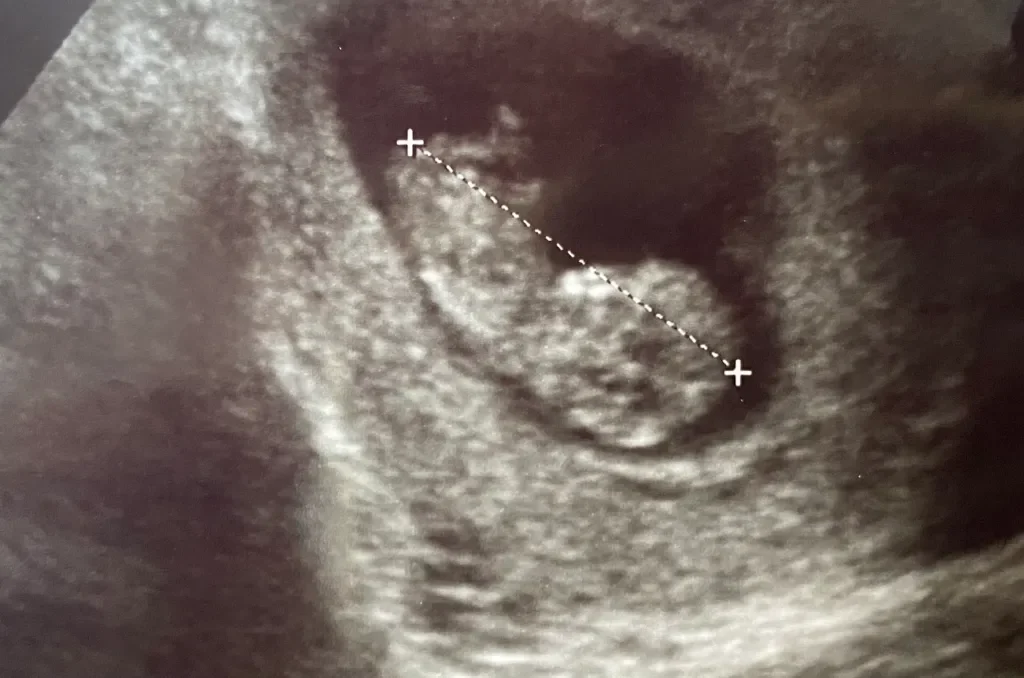

Baby Number 4 is On the Way

You surprised? We were too! All of our previous babies have been strategically planned out, but seeing as this has been a year of testing from the Lord for our family, it was only fitting that He would throw us this little curveball straight out of left field. A 4th child has actually been on our mind for the last year and a half, and honestly, we felt like God might be nudging us to foster or adopt, so we were in the midst of exploring that route. Then, the week we decided to list our house, we also found out we were expecting. It rocked our world. We were very shocked, and if we’re being honest, it took a little while for us to process it all, which is probably why it’s taken me 14 weeks to announce it (I announced all my other pregnancies at 9 weeks). With everything going on in our lives (starting homeschool, listing our house, selling our house, buying a new one), it was a lot to process, and we needed time. We were also really enjoying having this little family secret that was “just ours.” Here’s the video of when I found out, Zach found out, and when we told the kids. This was the first pregnancy where I found out without Zach there with me, and I was able to surprise him with the news. It was so fun to do that, and he was definitely surprised and happy. We shared the news with the kids soon after we found out, and they were all so excited. They have kept the secret somewhat well, and we are so proud of them. It has been so fun to share this little secret with them. It has been challenging keeping Emmie Grace from lifting my shirt in public to point out “baby” in mommy’s tummy. We are thinking we may not find out the gender this time, so that will be a fun surprise we’ve never experienced before. Looking back now, we see how God was working everything out, even the arrival of this new baby. Our new house is bigger than the one we had before, which we weren’t planning, but God knew there would be more babies and we would need the extra space. I think in our hearts we knew we were missing something, and we’re so excited to welcome this new blessing in June. God has taught us so much about trust, obedience, and patience this year, and even though this has been the toughest year of our lives, I really feel like our entire family has grown closer to each other and closer to the Lord through it all. Thank you all for sharing in our joy. Thank you for your love, prayers, support, and encouragement. We love you!